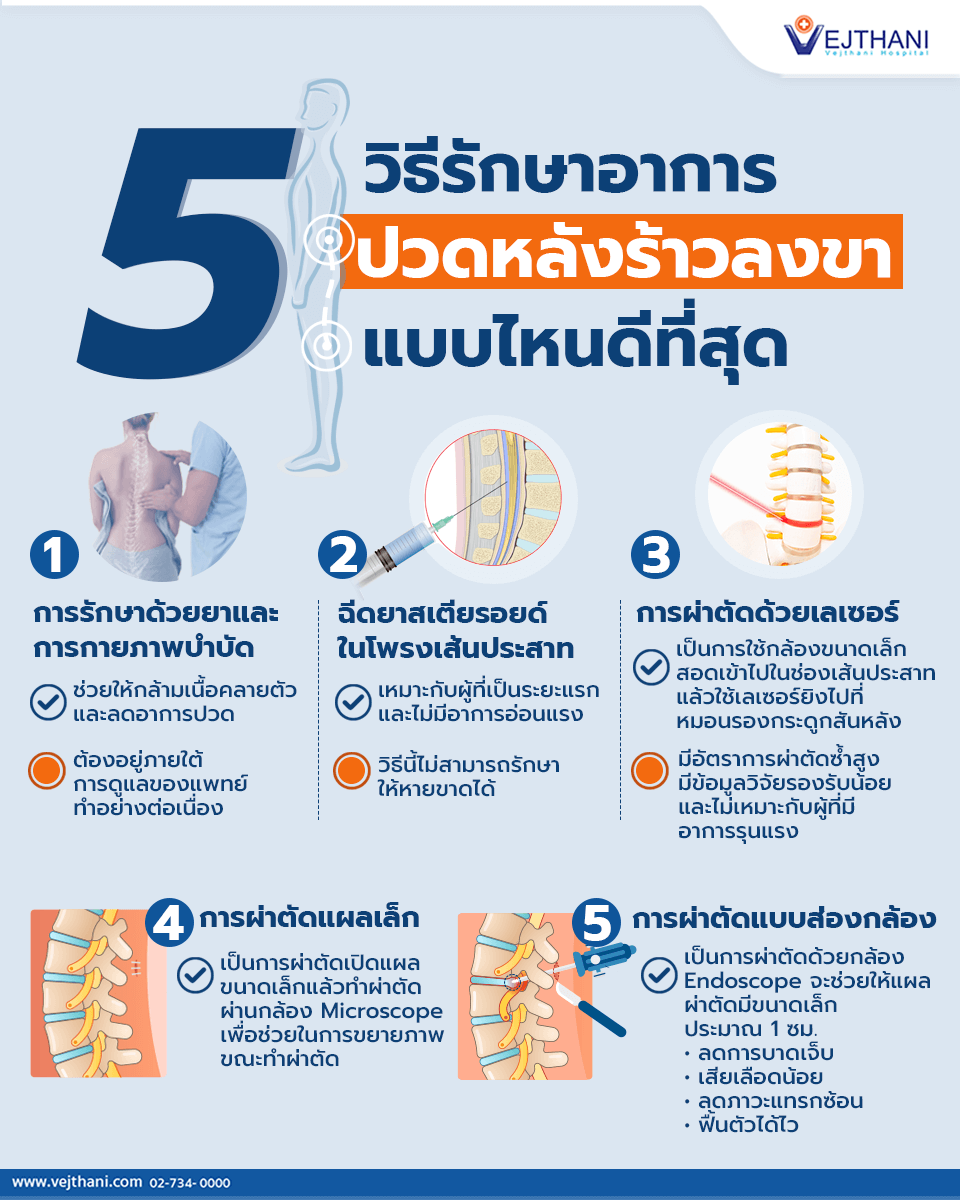

เท้าผิดรูป เกิดจากอะไร ต้องรักษาอย่างไร มีแบบไหนบ้าง มาดูกันครับ 3 แบบเท้าผิดรูปที่ทุกคนต้องสังเกต – โรงพยาบาลเวชธานี

3 แบบเท้าผิดรูปที่ทุกคนต้องสังเกต – โรงพยาบาลเวชธานี รูปมือวาดกระดูกเท้า PNG , การ์ตูน, ทาสีด้วยมือ, กระดูกเท้าภาพ PNG และ …

รูปมือวาดกระดูกเท้า PNG , การ์ตูน, ทาสีด้วยมือ, กระดูกเท้าภาพ PNG และ … หยุด 5 สิ่งทำลายกระดูกเท้าโดยไม่รู้ตัว – Vejthani Hospital